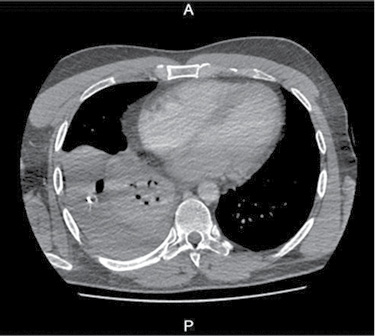

36 m. vyras P. D. atvyko į Gastroenterologijos skyrių patikslinti diagnozės planine kepenų biopsija. Praėjus 8 val. po procedūros, pacientas pajuto maudimą po dešiniuoju šonkaulių lanku punkcijos vietoje. Apžiūros metu pacientas buvo hemodinamiškai stabilus. Atlikus laboratorinius tyrimus, nustatyta saiki anemizacija (hemoglobinas – 128 g/l; norma – 135–160 g/l). Įtariant kraujavimą pilvaplėvėje, atlikta pilvo echoskopija: pilvo ertmėje laisvo skysčio nematyti, dešinėje pleuroje iki 4 cm laisvo skysčio ruožas. Konsultuota krūtinės chirurgo. Rekomenduota atlikti krūtinės ląstos rentgenogramą (Ro). Nustatytas beveik neoringas dešinysis plautis, pastebėta hidrotorakso požymių (1 pav.). Įtarus jatrogeninį hemotoraksą, krūtinės chirurgas atliko diagnostinę pleuros punkciją. Patvirtinus hemotorakso diagnozę, drenuota dešinė pleuros ertmė, išsiskyrė 400 ml kraujo. Tuo metu aktyvaus kraujavimo nenustatyta, hemodinamika išliko stabili, kartotiniuose laboratoriniuose tyrimuose – saiki anemizacija (hemoglobinas – 120 g/l). Atlikus kontrolinę rentgenogramą, nustatytas sumažėjęs skysčio kiekis pleuroje, buvo matyti kompresinių dešiniojo plaučio pakitimų. Įtariant sukrešėjusį hemotoraksą, atlikta skubi krūtinės ląstos KT (2 pav.), kuri patvirtino įtariamą patologiją. Tolesniam operaciniam gydymui pacientas perkeltas į Krūtinės chirurgijos skyrių. Atlikta skubi VATS (angl. video assisted thoracoscopic surgery). Operacijos metu pašalinta 1 000 ml krešulių, aktyvaus kraujavimo nenustatyta, diafragmos kupole rasta nedidelė hematoma. Pooperacinis periodas sklandus (3 pav.). Po trijų dienų geros būklės pacientas išleistas į namus.

2 pav. Krūtinės ląstos KT atlikus pleuros ertmės drenavimą (prieš operaciją)